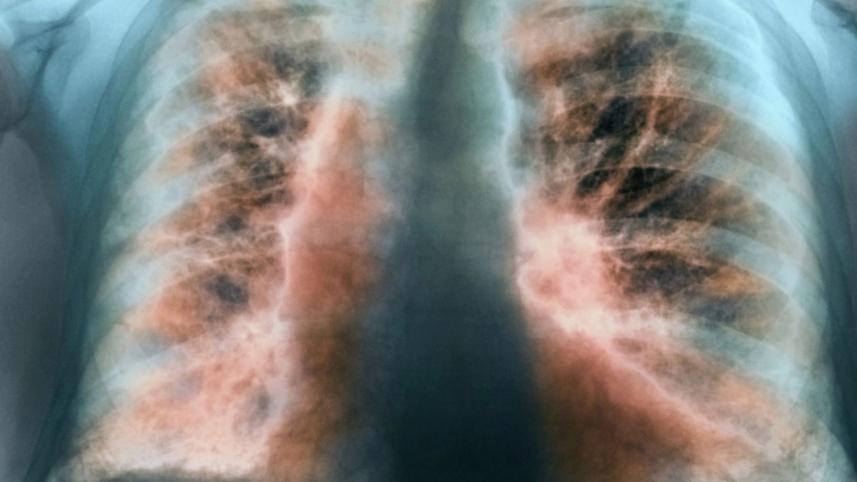

ফুসফুসের যে রোগে তিনি ভুগছিলেন, তার নাম ইডিওপ্যাথিক পালমোনারি ফাইব্রোসিস। নিরাময়যোগ্য নয়—এমন একটি রোগ ইডিওপ্যাথিক পালমোনারি ফাইব্রোসিস। ইডিওপ্যাথিক মানেই অজানা, আর রোগটি সম্পর্কেও অনেকেই খুব বেশি কিছু জানেন না। নীরবে বাড়তে পারে আইপিএফ যার ফলশ্রুতিতে মৃত্যু।

অধ্যাপক আতিকুর রহমান বলেন, ইডিওপ্যাথিক পালমোনারি ফাইব্রোসিস (আইপিএফ) ফুসফুসের দীর্ঘস্থায়ী একটি রোগ। ফুসফুসের স্বাভাবিক কাজ অক্সিজেন আদান-প্রদান করা। শ্বাস নেওয়ার সময় ফুসফুস প্রসারিত হয় কারণ ফুসফুসের টিস্যু বা তন্তগুলো সাধারণত নরম, স্থিতিস্থাপক থাকে। ইডিপ্যাথিক পালমোনারি ফাইব্রোসিস হলে ফুসফুসের টিস্যুগুলো ক্ষতিগ্রস্ত হয়, সেগুলো শক্ত হয়ে যায়, বিভিন্ন দাগ পড়ে। আইপিএফের কারণে রক্তে অক্সিজেন আদান-প্রদানে ফুসফুসের সক্ষমতা কমে যায় এবং শ্বাসকষ্ট শুরু হয়।

ইডিওপ্যাথিক পালমোনারি ফাইব্রোসিস হলে শ্বাসকষ্ট হয়, কারণ অক্সিজেনের অভাব দেখা দেয়। অক্সিজেনের অভাবে দেহের বিভিন্ন অঙ্গে অক্সিজেন পৌঁছাতে পারে না। ফুসফুস সম্পূর্ণভাবে অক্সিজেন সরবরাহ করতে না পারার কারণে ধীরে ধীরে অক্ষম হয়ে পড়ে। ফুসফুসের অক্ষমতার কারণে ফুসফুসে রক্তচাপ বাড়ে, যেটাকে পালমোনারি হাইপারটেনশন বলে। এই পালমোনারি হাইপারটেনশনের কারণে হার্ট বা হৃদযন্ত্রের ওপর চাপ পড়ে। অক্সিজেনের স্বল্পতায় শ্বাসকষ্টের কারণে স্বাভাবিক জীবনযাপন ব্যাহত হয়।